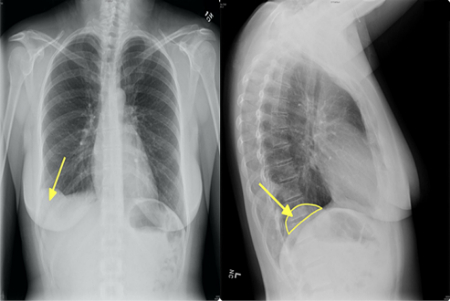

هامارتوماها اغلب به طور اتفاقی در تصویربرداری برای مشکل دیگری کشف میشوند. برای تأیید تشخیص ممکن است نیاز به آزمایشهای تصویربرداری زیر باشد:

• سیتی اسکن (CT scan)

• رادیوگرافی (اشعه ایکس)

3. هامارتومای ریه چقدر شایع است؟

شایعترین هامارتومای خوشخیم ریه است (حدود ۷۰–۸۰٪ تومورهای خوشخیم ریه).

بیشتر در بزرگسالان ۴۰–۶۰ سال دیده میشود و در مردان شایعتر است.

4. آیا هامارتومای ریه باید عمل شود؟

اگر کوچک باشد و علامتی نداشته باشد → معمولاً فقط پیگیری با سیتی اسکن هر ۶–۱۲ ماه. اگر بزرگتر از ۲.۵ سانتیمتر باشد، در حال تومور باشد یا علائم (سرفه، تنگی نفس) بدهد → جراحی (معمولاً با VATS یا جراحی کمتهاجمی).